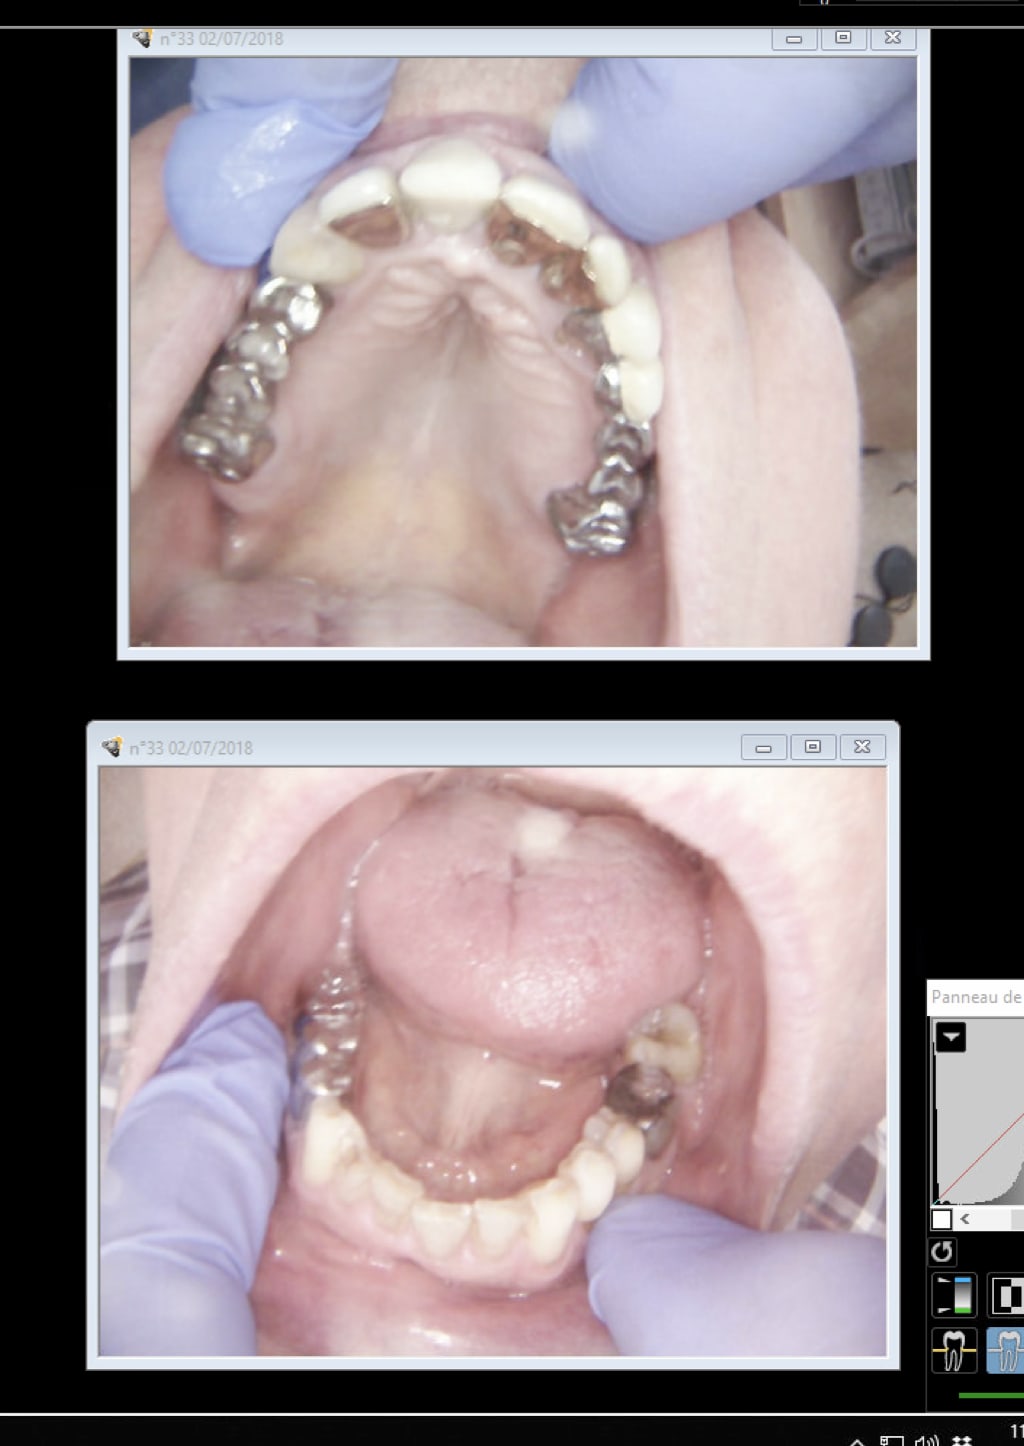

Vu vend, suite à une cellulite, ma pano est justifiée, je pense .

2 dents mobiles, en bas à gauche retirées sans radio, par un confrère, semble-t-il avec aucune douleur, mais parce qu'elle elle gênait, il y a 1 mois.

P1 wpcg4r - Eugenol

Tu as les 2 avec le TIB. Signes d'appels + antécédents de soins intensifs. Un cas comme le tien ça ne se voit pas tous les jours.